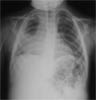

A 2 ½-year-old child is hospitalized with a 1-month history of worsening persistent cough. She was initially treated with a 5-day course of oral amoxicillin, and her symptoms abated somewhat. However, for the past week, she has experienced high fever (temperatures up to 38.3°C [101°F]) and chills associated with right-sided pleuritic chest pain.

Chest films are ordered.

The chest radiographs show alarge cavitary lesion in the rightupper chest, with air-fluid level anda bulging fissure. This finding,in a patient with persistent coughand fever, strongly suggests lungabscess, A.